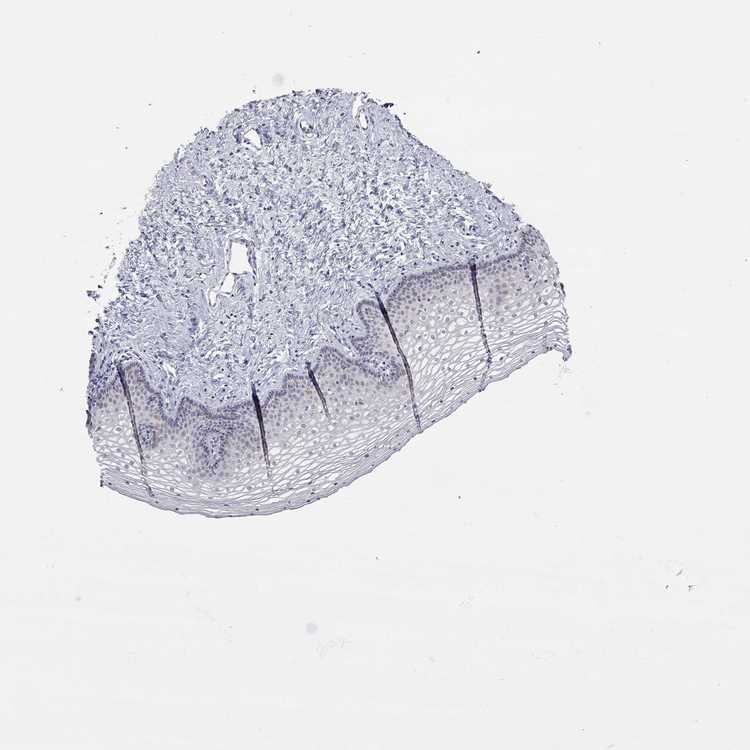

TISSUE PRIMARY DATA VAGINA Show tissue menu

VAGINA - Antibody stainingi

Antibody staining in the annotated cell types in the current human tissue is reported as not detected, low, medium, or high, based on conventional immunohistochemistry profiling in selected tissues. This score is based on the combination of the staining intensity and fraction of stained cells.

Each image is clickable and will lead to virtual microscopy that enables deeper exploration of all samples and also displays staining intensity scores, fraction scores and subcellular localization as well as patient and tissue information for each sample.

Antibody HPA008410Antibody HPA027821

Squamous epithelial cells MediumNot detected